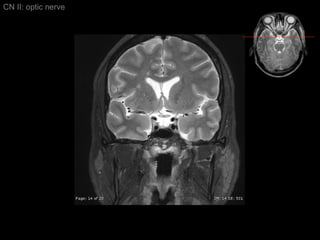

CN II: optic nerve